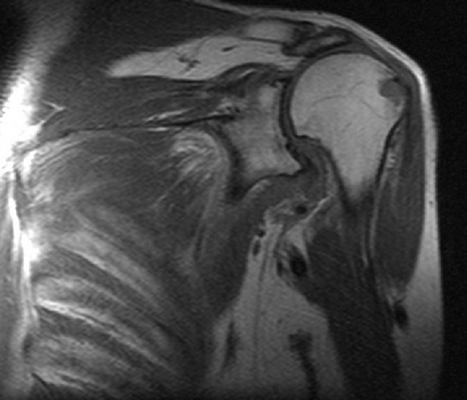

МРТ плечевого сустава, что показывает?

МРТ плечевого сустава

МРТ плеча

Расшифровка фото снимков МРТ плечевого сустава